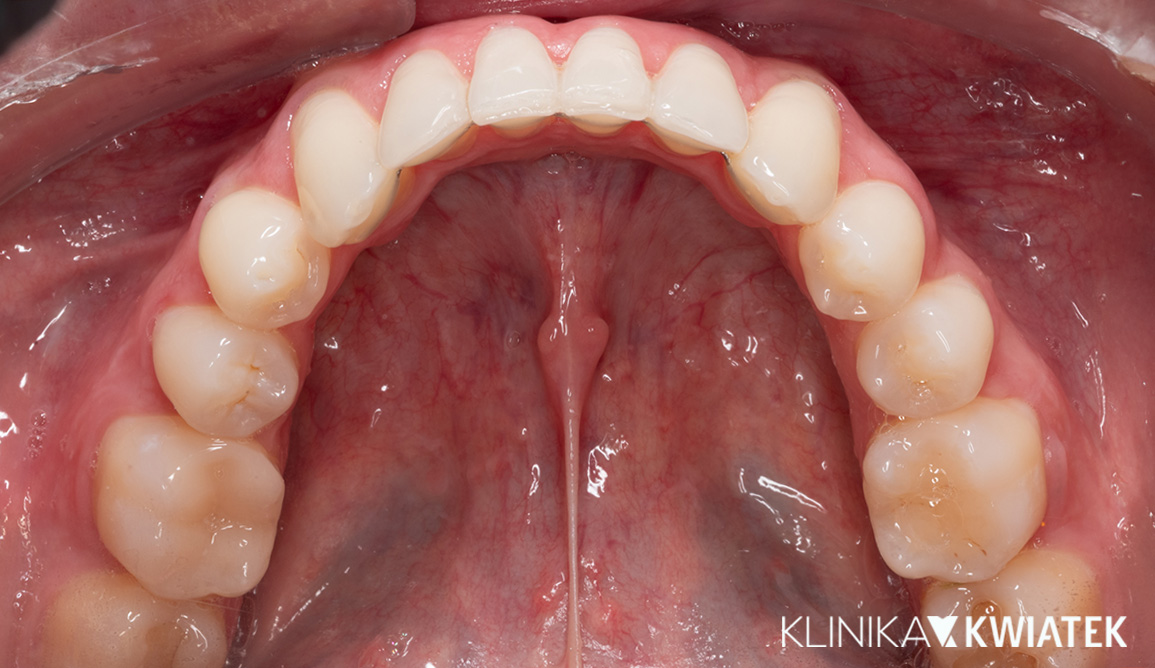

PRZED

PO

Pacjentka zgłosiła się z licznymi ubytkami, znacznym starciem zębów oraz objawami przeciążenia zgryzu wynikającymi z wieloletniego zaciskania i zgrzytania. Po pełnej diagnostyce przeprowadzono higienizację, leczenie zachowawcze, endodontyczne i szynoterapię, a następnie ortodoncję oraz finalną odbudowę estetyczno-protetyczną wszystkich startych powierzchni zębów. Efektem jest stabilny, zdrowy zgryz, prawidłowa praca stawów oraz harmonijny, trwały i estetyczny uśmiech Pacjentki.